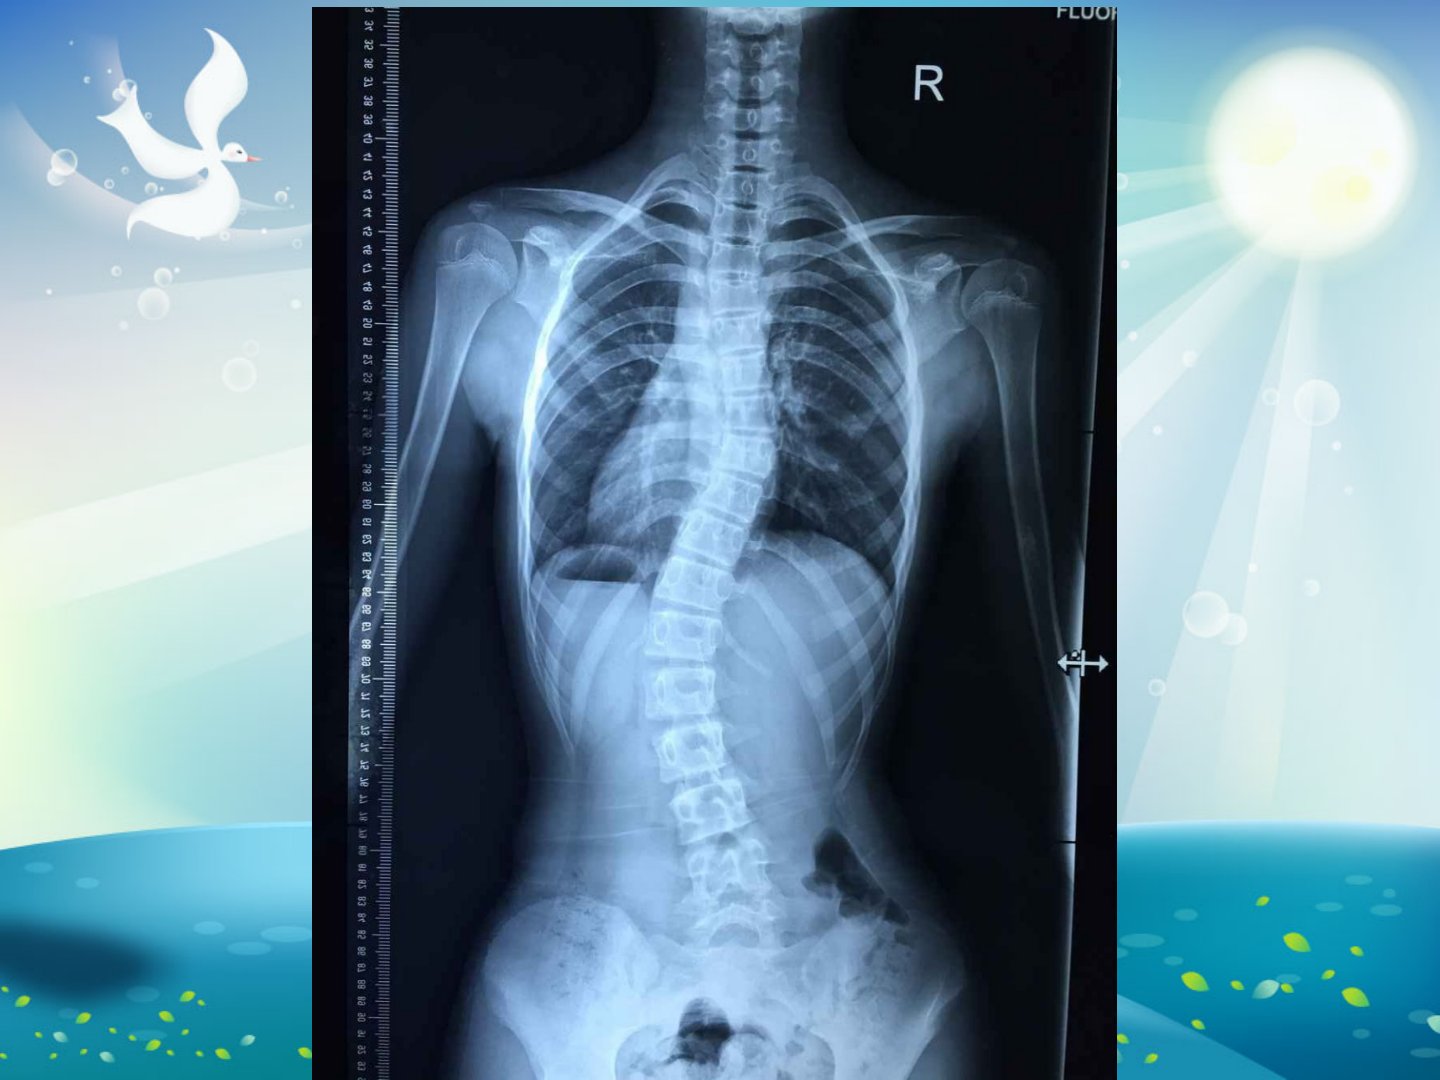

特发性脊柱侧凸指青少年期(1018岁)发病、原因不明的脊柱侧凸10岁前发病称早发特发性脊柱侧凸其中03岁为婴儿型49岁为幼儿型。10岁前发病但青少年期诊断的需注明婴儿或幼儿期发病;青少年期发病但成人期畸形仍进展的诊断为成人特发性脊柱侧凸。诊断时需拍摄站立位正位X线片注意消除下肢不等长影响。Cobb角测量是诊断关键取站立位X线片上侧弯头尾倾斜最大的椎体沿其上下终板画线夹角即为Cobb角大多数学者以10度为诊断标准。CSVL线是分析脊柱侧凸的重要线需准确画出。肩平衡通过经两侧肩锁关节作垂线测量上下水平线垂直距离来定义。根据顶锥位置脊柱侧凸可分为胸弯、胸腰弯和腰弯。主弯是Cobb角度最大的弯确定主弯后其上下代偿弯在仰卧位Bending像25度时称结构性弯。